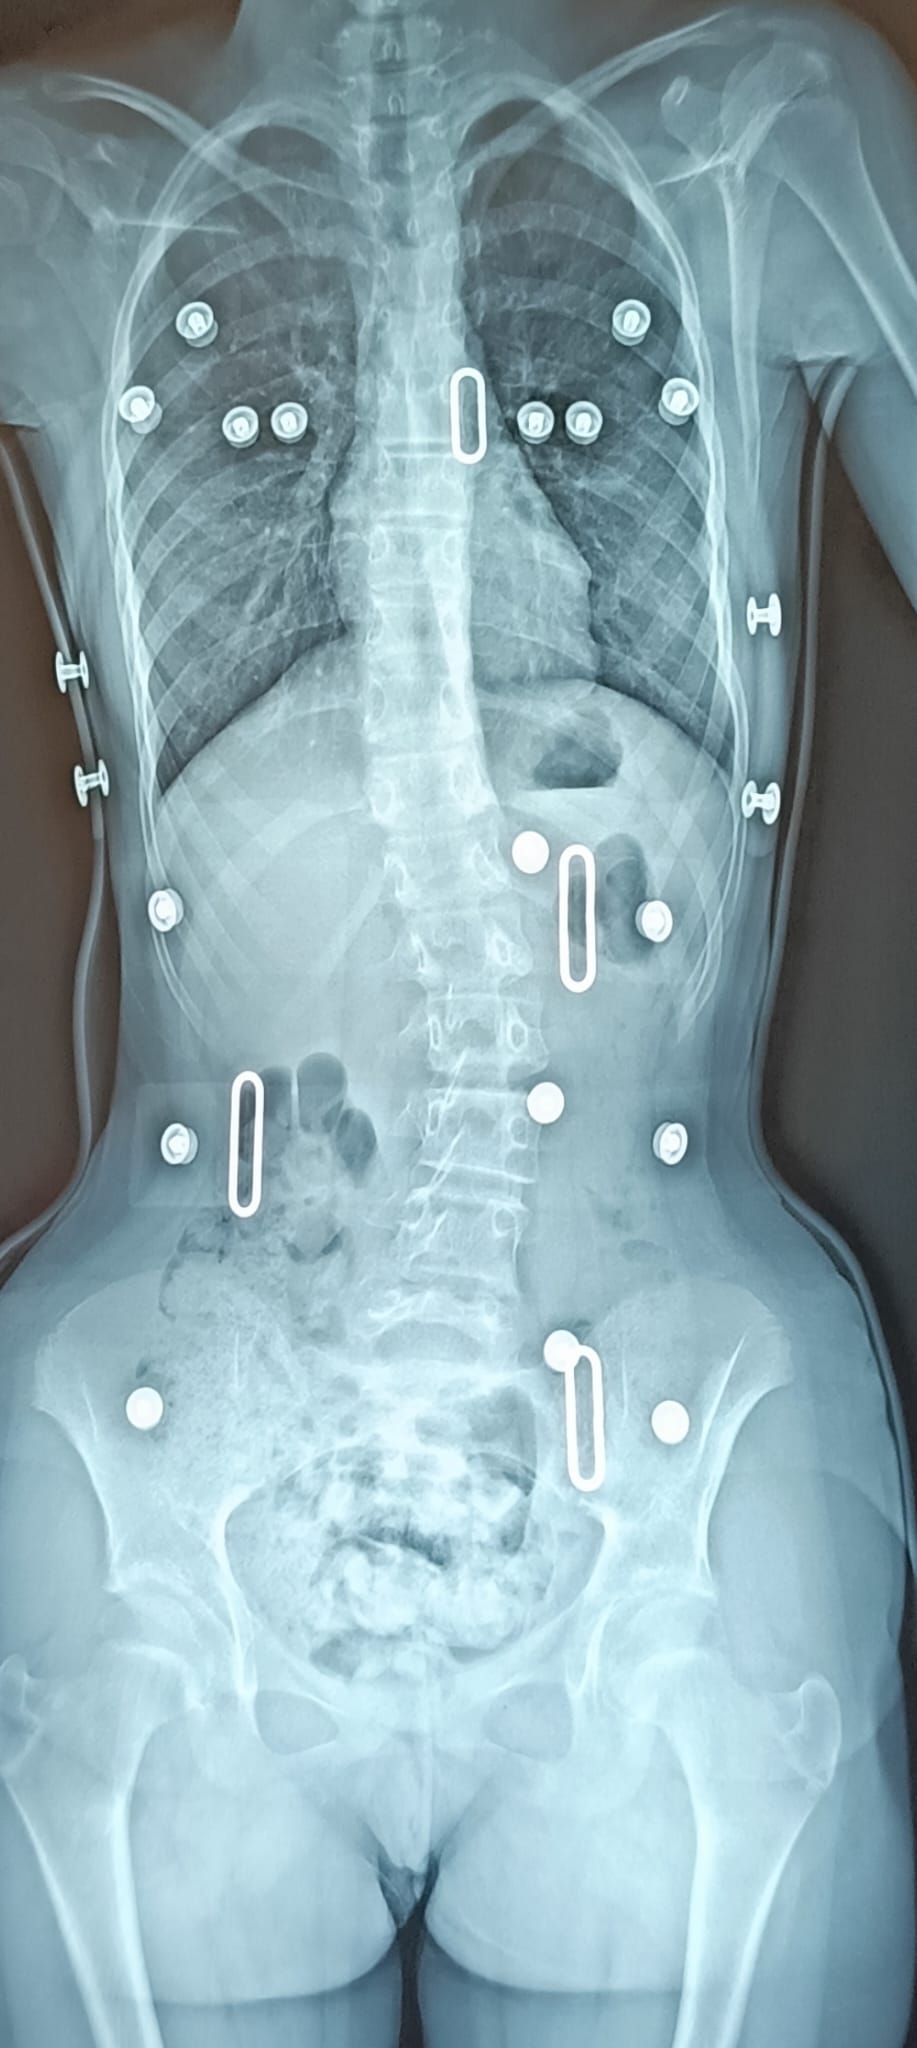

Le traitement se fait par appareillage au moyen d’un corset orthopédique sur mesure, moulé sur le corps et conçu de manière à permettre une croissance normale du rachis en corrigeant les déformations existantes.

Chaque corset est réalisé et adapté selon la morphologie du patient. Il tient compte de la déformation du rachis, du poids et de la taille de celui-ci, ainsi que de la prescription médicale. Selon la déformation du rachis et le modèle de corset prescrit, les temps de port de ce dernier peuvent être variables. De même des ajustements peuvent être réalisés selon l’évolution de la pathologie et de la morphologie du patient.